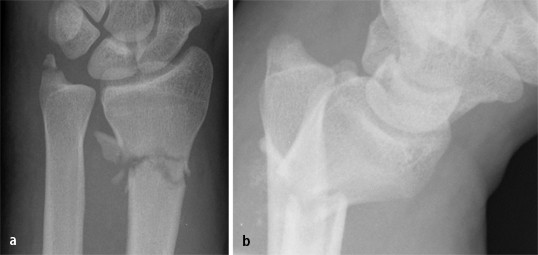

A Fracture Of The Tip Of The Ulnar Styloid With A Stable Dru Joint Download Scientific Diagram

Figure 2 Ausrissfraktur Des Processus Styloideus Ulnae Bei Der Distalen Radiusfraktur Springerlink